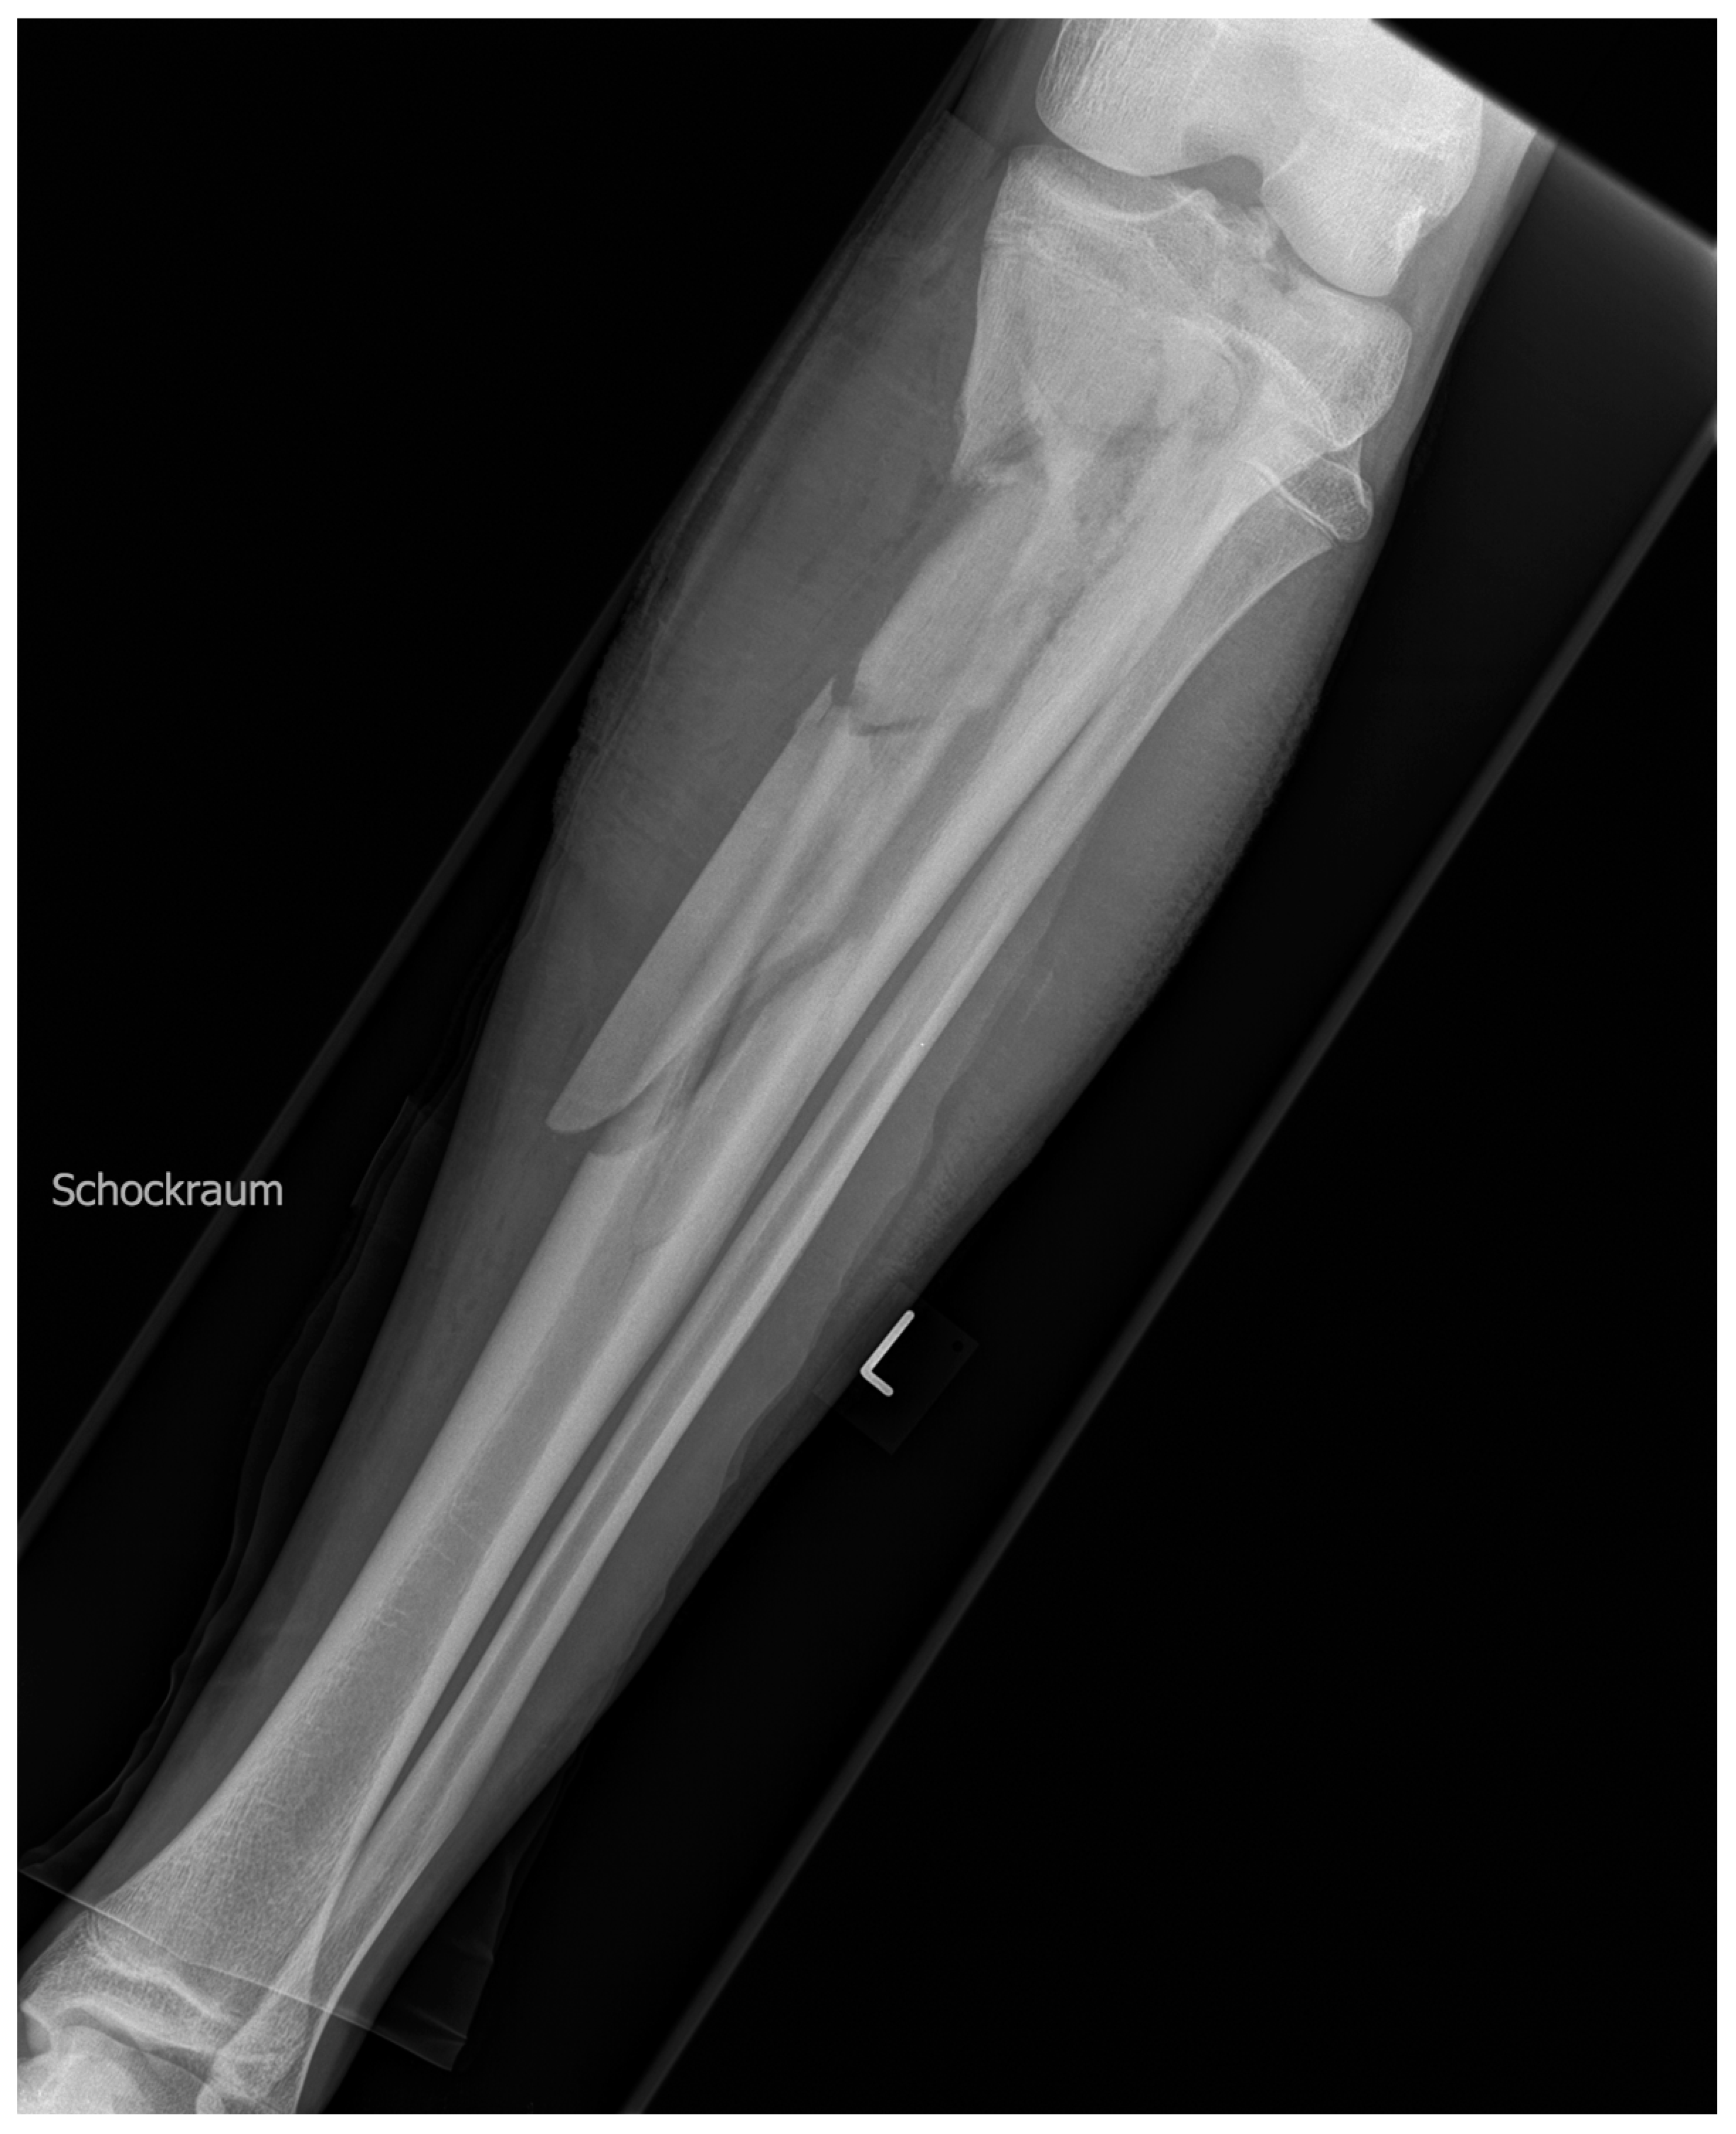

2. Case Description